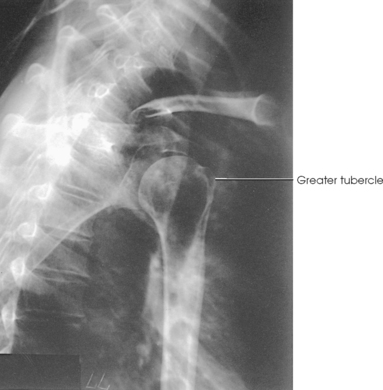

The lesser tubercle is situated on the anterior surface of the bone, immediately below the anatomic neck (Figs. 5-6 and 5-7; see Fig. 5-5). The tendon of the subscapular muscle inserts at the lesser tubercle. The greater tubercle is located on the lateral surface of the bone, just below the anatomic neck, and is separated from the lesser tubercle by a deep depression called the intertubercular (bicipital) groove. The superior surface of the greater tubercle slopes posteriorly at an angle of approximately 25 degrees and has three flattened impressions for muscle insertions. The anterior impression is the highest of the three and affords attachment to the tendon of the supraspinatus muscle. The middle impression is the point of insertion of the infraspinatus muscle. The tendon of the upper fibers of the teres minor muscle inserts at the posterior impression (the lower fibers insert into the body of the bone immediately below this point).

Fig. 5-14 A, AP shoulder, external rotation humerus: greater tubercle in profile (arrow). B, AP shoulder, neutral rotation humerus: greater tubercle (arrow).

External rotation: The greater tubercle of the humerus and the site of insertion of the supraspinatus tendon are visualized (see Fig. 5-14, A).

Neutral rotation: The posterior part of the supraspinatus insertion, which sometimes profiles small calcific deposits not otherwise visualized (see Fig. 5-14, B), is seen.